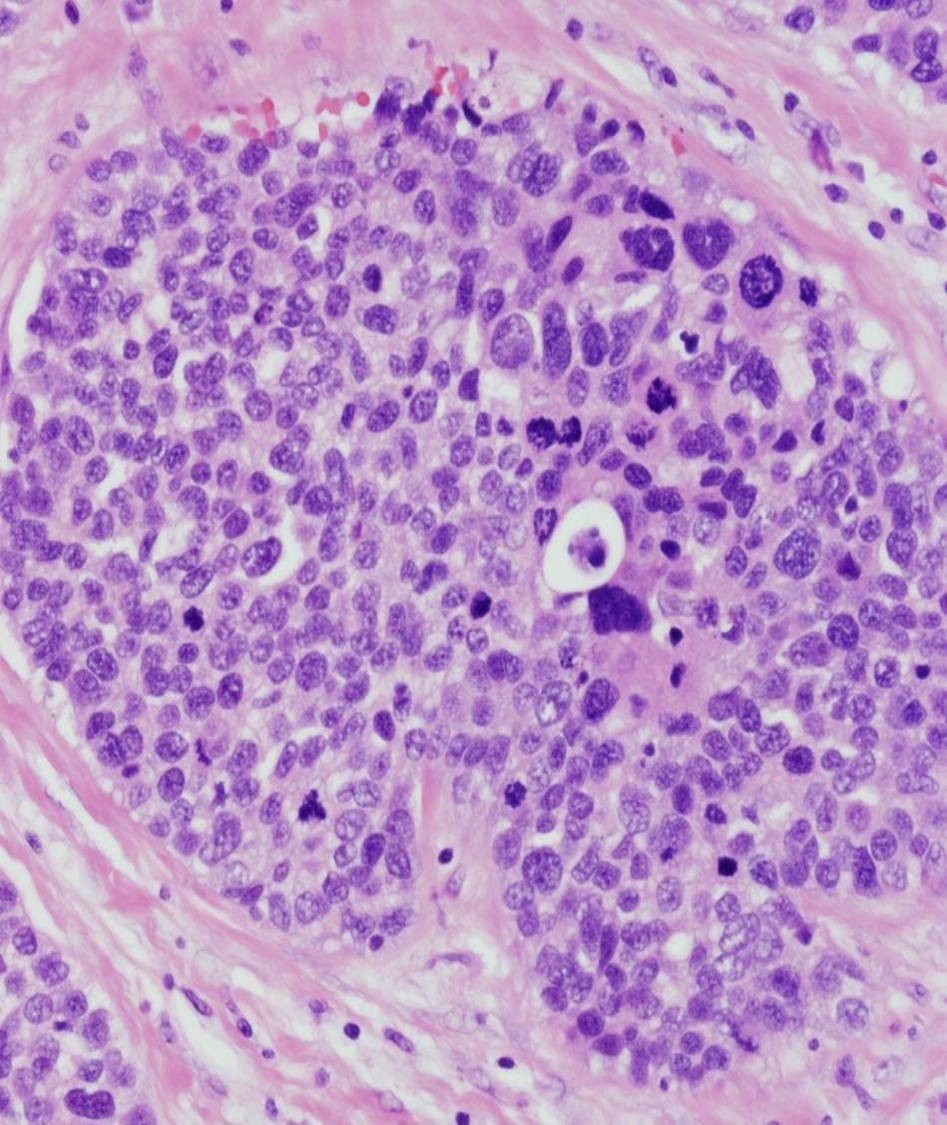

What are 3 abnormal findings in the slide shown below?

this mimics breast carcinoma, usually presenting as an abnormal mammographic finding or palpable mass, and often follows a recent history of trauma or surgery

fat necrosis; characterized acutely by necrotic adipocytes with hemorrhage and inflammation and over time will be mixed with foamy macrophages